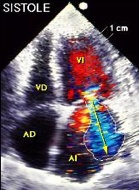

Stacks Image 3263

Ecocardiografía 2D. Marcada dilatación de las cavidades cardíacas.

Técnica doppler:

• Para valorar el flujo se utiliza el doppler color:

• Se detecta insuficiencia mitral, que suele ser ligera o moderada. No es la causa primaria de la miocardiopatía.

Stacks Image 3277

Doppler color